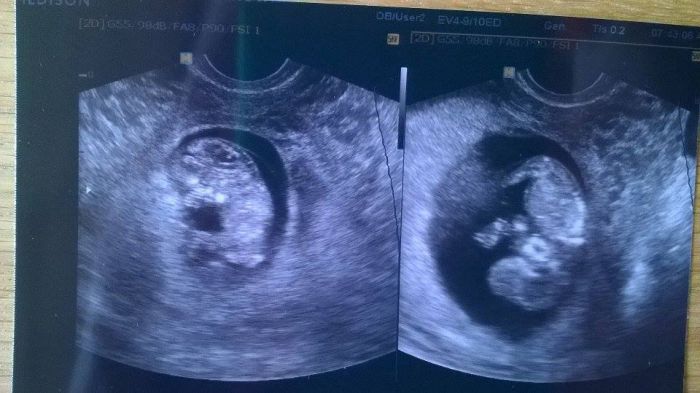

Ahoj holky, tak hlásím, že máme 4 cm. Odpovídáme tomu 10tt+6 - 11tt+0

tlak jsem měla 130/70, miminka se tam uplně točily, vrtěly, protahovaly, to nemělo chybu

vzala mi 6 zkumavek krve, a screeningový UTZ přesně za 14 dní ve čtvrtek

tak se těším, snad se dovíme pohlaví, a hlavnmě snad bude vše OK!!!!!!!!!!!!!!!!!!!!!

Přikládám foto. Je nic moc kvality, moc se vrtěly..... :)

Už nešly dát ani spolu na jednu fotku, chi chi